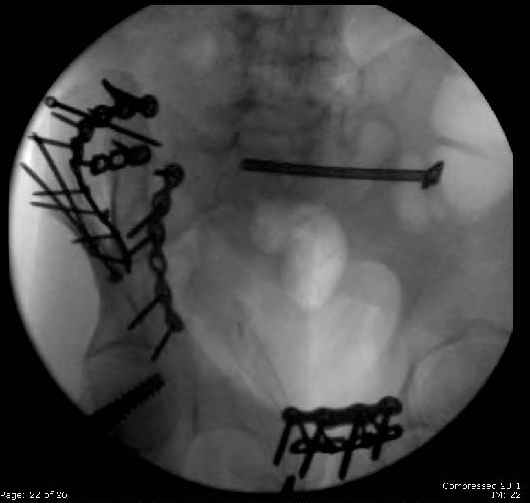

Here are the postop fluoros.

First exposed symphysis & clamped w/Faraboeuf as close to anatomic as possible.

Then extended to R ilioinguinal,really just the lateral window.

Reduced the triangular wedge piece of iliac wing to posterior intact ilium (crescent), held w/k-wire, then used 3-hole push plate to keep from moving, lagged from lat-med w 3.5 screw.

Then 6-hole plate along brim with 1 screw in R sacral ala. Then lagged 2 screws along crest A --> P. finally 10-hole plate along inner aspect of crest. R posterior ilium still a bit stepped off.

Symphysis then 'fine-tuned' & reduced as close as possible to anatomic (but, still with forward rotation of R hemipelvis - or, is it extension?) Accepted that amount of deformity and plated symph

with 4-hole symphyseal plate.

Fluoroed L SI joint and it seemed stable, but wide. So, applied c-clamp to try to squeeze down L SI joint (and note, on the last slide attached, that it's still wide), and got it closer. Single perc Iliosacral screw 40mm thread.

Applied second plate anteriorly on symphysis as I wasn't confident L SI was as stable as it could be and wanted to protect it better.

Thoughts? Thanks for the advice, it's appreciated.